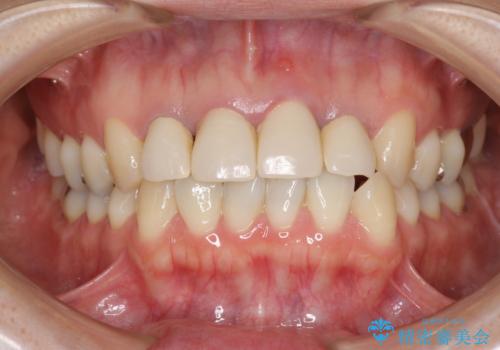

金属のフレームを用いるクラウンは色調が暗くなる傾向にありますが、セラミッククラウンに置き換えたことで自然な明るさ、審美性を取り戻すことができました。

黒っぽい歯ぐきを改善したい メタルフリーセラミック治療

- 20代女性

- 2ヶ月